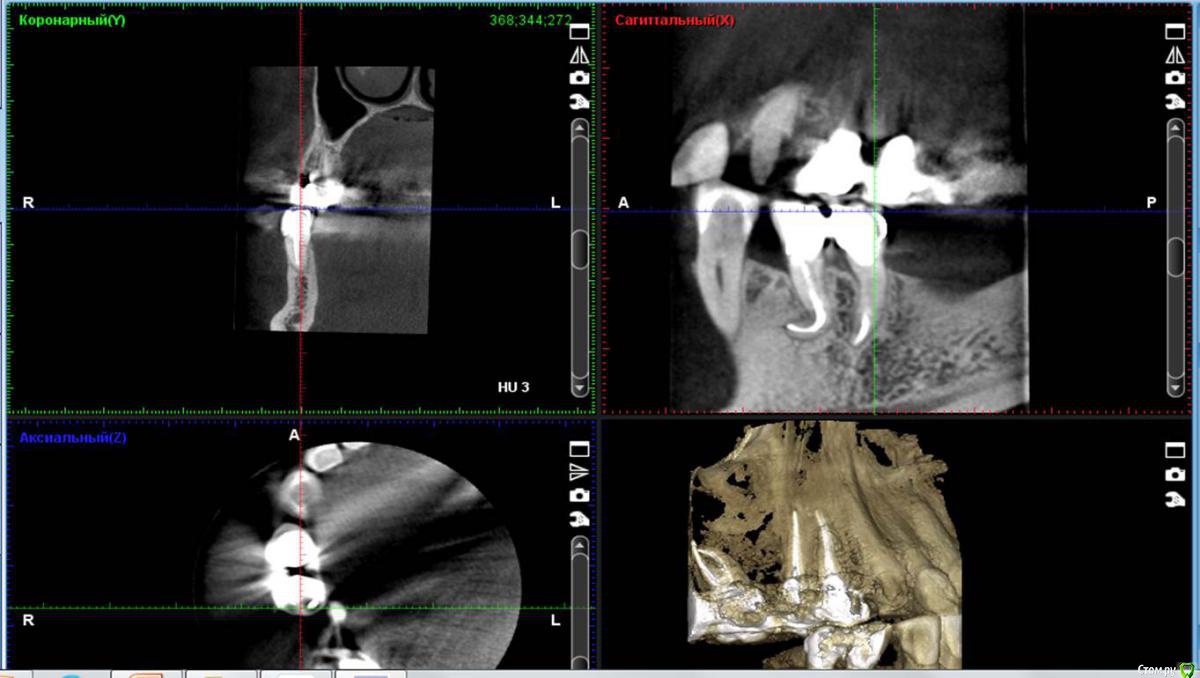

Сегодня пришёл мой давнишний  пациент... по поводу возможной имплантации....

и вот какой ...крючок на КТ ,,я обнаружил (вспомнил) ..Эндолечение 4.5  проводилось 6-7 лет назад :)

Пока полет нормальный